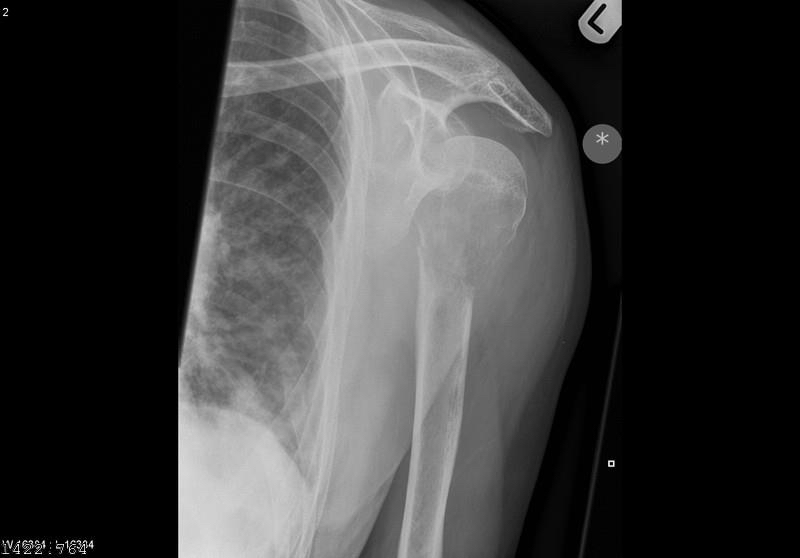

What is this?

A

Bony mets